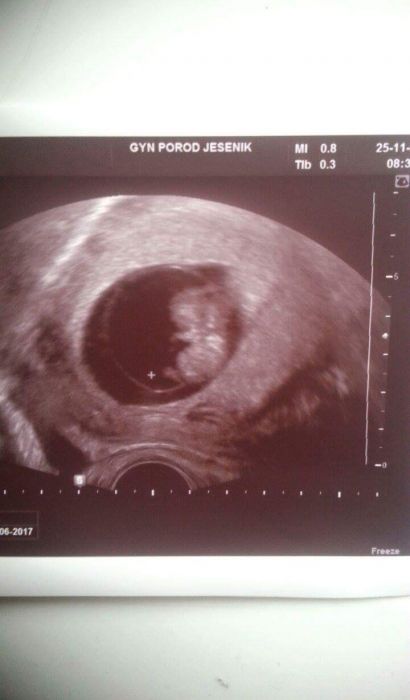

Mileno, hezky snimek, gratuluju!

Edith: Děkuji, je úžasné prcka vidět, v červnu tento rok jsem musela skrz zámlkly potrat v 11tt na revizi, tentokrát je všechno jinak, v pořádku ♡